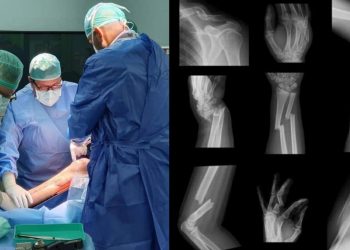

तुटलेली हाडे मजबूत जोडणाऱ्या हलक्या इम्पांटचा भारतात शोध

मुक्तपीठ टीम देशात पहिल्यांदाच आता हाडांना जोडण्यासाठी थ्री-डी मॉडेल इम्प्लांटचे तंत्रज्ञान शोधण्यात आले आहे. या तंत्रज्ञानानुसार रॉड, प्लेट किंवा ...